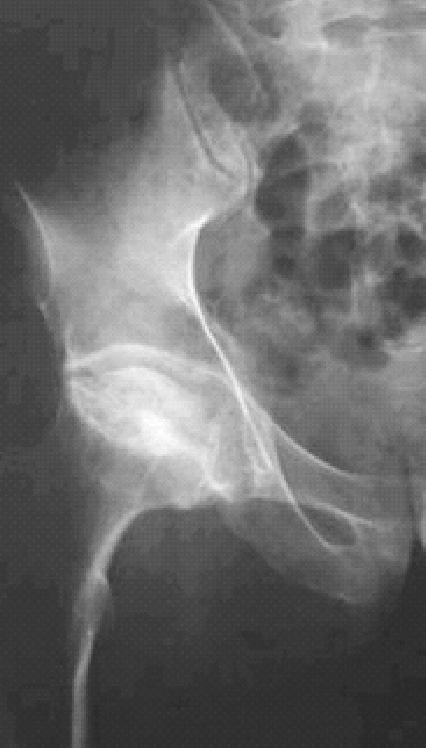

股骨头坏死(图25)是由于各种原因导致骨的血液供应中断以后骨细胞和骨髓成分死亡,继而出现股骨头结构改变引起股骨头塌陷和跛行等髋关节功能障碍的一种难以治疗的病症,为常见的骨关节病之一。大多因髋部外伤、酗酒、使用糖皮质激素引起,也可以由血液病、减压病、烧伤、冻伤等疾患引起。在临床上,时常可以见到股骨头坏死被误诊为腰椎间盘突出症的,有的做了腰椎的手术,疼痛还是如旧,回过头来检查,才发觉股骨头坏死是真正的“元凶”。

图25 股骨头坏死X线片

分析原因,一般有两个方面可以导致误诊:一者,闭孔神经由腰神经分出,在股骨颈附近通过,被坏死的股骨头刺激或者关节内压力增高所刺激,出现类似腿痛的症状;二者,股骨头坏死后,下肢软组织的力学改变,导致下肢甚至牵扯到腰部的软组织劳损,出现类似的腰腿痛症状。因此,在诊断腰椎间盘突出症时不能忽视对股骨头坏死的排除。